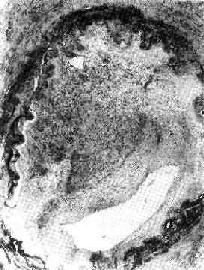

图3-6 机化的血栓

血管腔内的血栓已为肉芽组织取代有再通现象